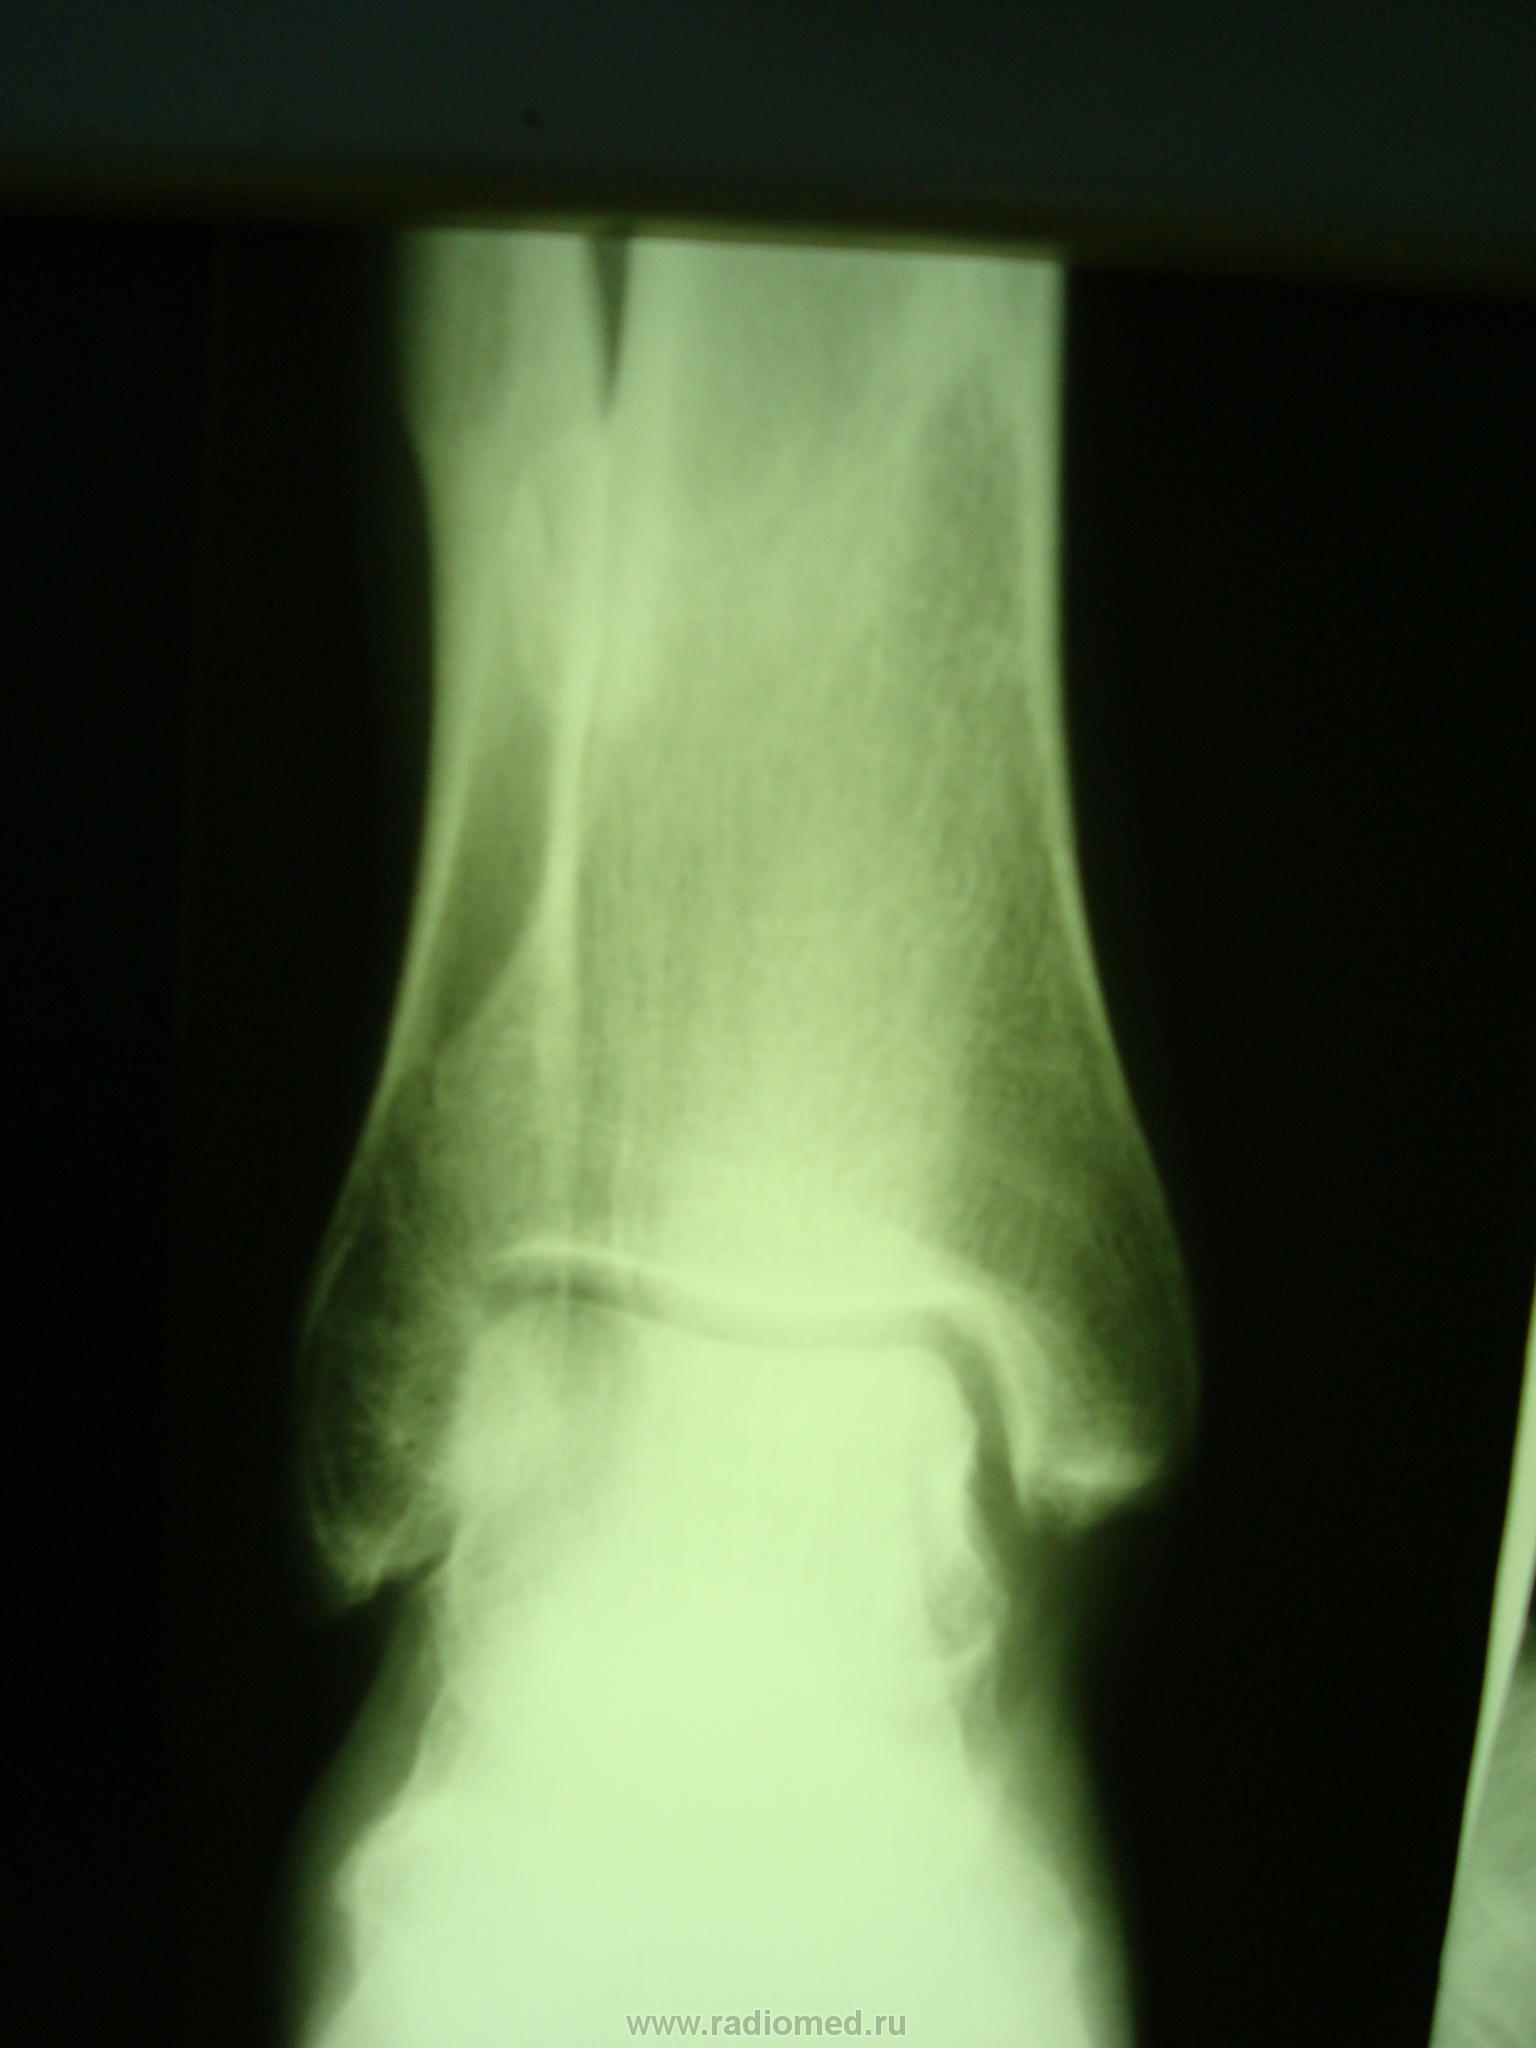

В анамнезе перелом костей голени год назад. Несколько месяцев назад появились боли в области голеностопного сустава.Интересует природа округлого образования в межберцовом промежутке.

На обызвествление поднадкостничной гематомы не похоже?

Структура костная плохо видна. Я к примеру, не нахожу признаков перелома костей голени. А так, можно предположить остеому, если возраст молодой.

Определяется косой консолидированный перелом дистальной трети диафиза берцовых костей. При переломе делали же снимки, запросите архив, было ли там это овальное образование? Можно доп.снимок с ротацией кнутри, чтоб на контур вышло. Может это лишь реактивное посттравматическое разрастание костной ткани.

Спасибо коллега, то что вы написали про переломы  "попали в точку" и за дельные мысли, запрость снимки, через кокое-то время после травмы. Скорее всего, это какая-то посттравматическая  метаплазия  мягких тканей в костную.

Термин доморощенный, но посттравматические изменения близ линии перелома нередки. Периостальная реакция, быть может. Без явной травмы встречаются обызвествления межберцового промежутка. У Рейнберга: "Однократная травма может осложниться также обызвествлением и окостенением одних только сухожилий и других околосуставных мягких тканей",  в главе об оссифицирующем миозите. Я не утверждаю, что тут нет остеомы, как по мне так нужна еще одна проекция и анализ снимков во время, после травмы.

А не проще-сросшиеся переломы диафизов нижней трети костей голени с формированием межберцового синостоза...